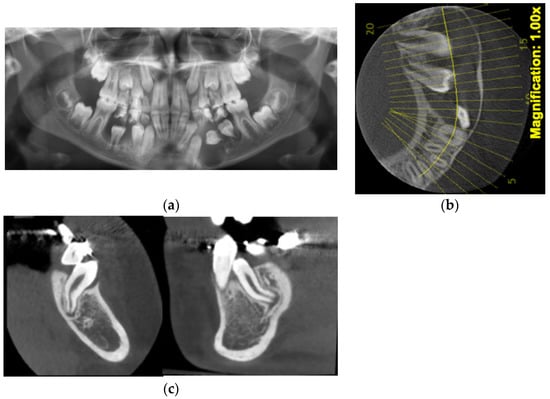

Figure 5.

(a) Bilateral impaction of lower first and second molars associated with DCs. All four molars presenting abnormal root development, uncorrelated with the age of the patient. (b) Orthodontic traction applied from a lingual arch to aid the eruption of the lower first molars. (c) Progress records at four months after the removal of both mandibular third molars.

The aforementioned is a rare case of bilateral mandibular DC-associated first and second molars, impaction, and root DL of the first molar. The DCs could be the cause of a root DL because the tooth did not erupt, and the roots were constrained to develop in a closed area of dense bone. Another factor that could determine the first molar’s root DL was the pressure applied by DCs of the second molar’s and probably the third molar’s buds. Because the root DL also affected the canine, it could also be considered the genetic etiology of root DL in a DAP patient.

Figure 6.

(a) Impaction of the central incisor, congenitally missing lateral incisor, and a supernumerary tooth were noticed on the initial panoramic X-ray and CBCT. (b) Panoramic X-ray showing the root DL of all the incisors. (c) CBCT—upper right impacted canine presenting a DC.

Along with the supernumerary tooth extraction, the marsupialization of the DC was performed, and the central incisor started its eruption. After a while, a second surgical intervention was done to bond an attachment for orthodontic traction of the central incisor, which had an abnormal mesiodistal width—gigantism. Because of its size, the space for the missing right lateral incisor was closed, and there was not enough space for the canine, which remained impacted, included in a DC. The new panoramic X-ray showed the root DL of all the incisors, being more evident on the left side (Figure 6b). For the left central incisor, the root DL could be explained by the closed contact of DC-associated right central incisor DC with its root at different vertical levels, as seen on the CBCT. For establishing the treatment plan, the long-term prognosis of the right canine had to be taken into consideration with the aid of a new CBCT. It was noted on the CBCT that the canine is impacted, included in a bigger DC than initially seen, and with root DL (Figure 6c). The case described above was a DAP of genetic origin, impaction of the central incisor, congenitally missing lateral incisor associated with canine impaction, and DCs including impacted teeth. The root DL of the incisors and right canine could be caused in this case not only by DC and deep impaction of the central incisors, but also by genetic causes.